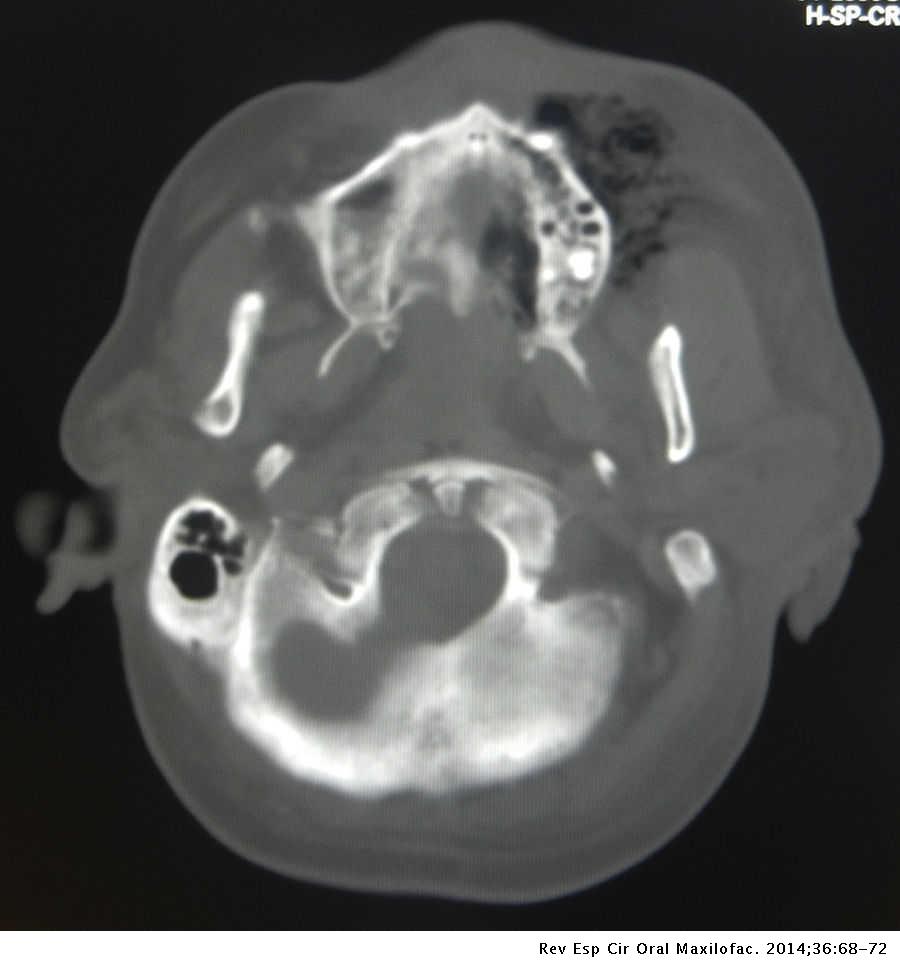

Mucormicosis Rinocerebral De Origen Dental, Reporte De Un Caso Clínico

Mucormicosis rinocerebral de origen dental, reporte de un caso clínico www.elsevier.es

Mucormicosis rinocerebral de origen dental, reporte de un caso clínico ...